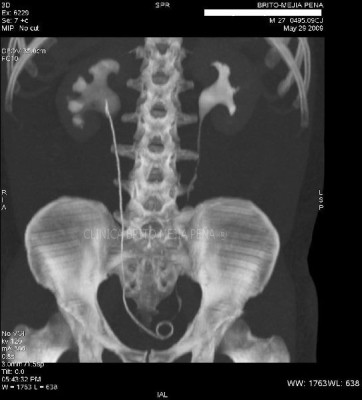

Urotac fase excretoria

Post Image